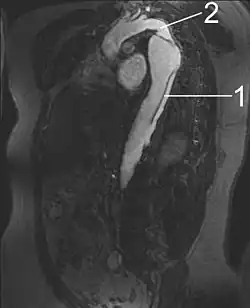

Arterial dissections become life-threatening when growth of the false lumen prevents perfusion of the true lumen and the related end organs. For example, in an aortic dissection, if the left subclavian artery orifice were distal to the origin of the dissection, then the left subclavian would be said to be perfused by the false lumen, while the left common carotid (and its end organ, the left hemisphere of the brain) if proximal to the dissection, would be perfused by the true lumen proximal to the dissection.

1 Aorta descendens with dissection

2 Aorta isthmus

Vessels and organs that are perfused from a false lumen may be well-perfused to varying degrees, from normal perfusion to no perfusion. In some cases, little to no end-organ damage or failure may be seen. Similarly, vessels and organs perfused from the true lumen but distal to the dissection may be perfused to varying degrees. In the above example, if the aortic dissection extended from proximal to the left subclavian artery takeoff to the mid descending aorta, the common iliac arteries would be perfused from the true lumen distal to the dissection but would be at risk for malperfusion due to occlusion of the true lumen of the aorta by the false lumen.